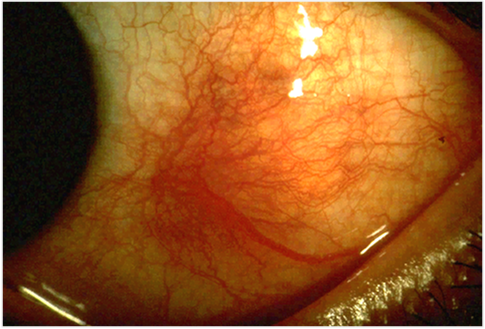

Scleritis eye inflammation

By Kribz (Own work), CC BY-SA 3.0, via Wikimedia Commons